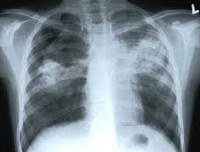

Рентгенография грудной клетки при различных формах туберкулеза органов дыхания у детей позволяет визуализировать изменения во внутригрудных лимфоузлах или легких. При необходимости исследование дополняется линейной или компьютерной томографией органов грудной полости. Бронхоскопия ребенку необходима для оценки косвенных признаков туберкулезного процесса (выявления признаков эндобронхита, деформации трахеи и бронхов увеличенными лимфоузлами) и получения смывов для исследований.